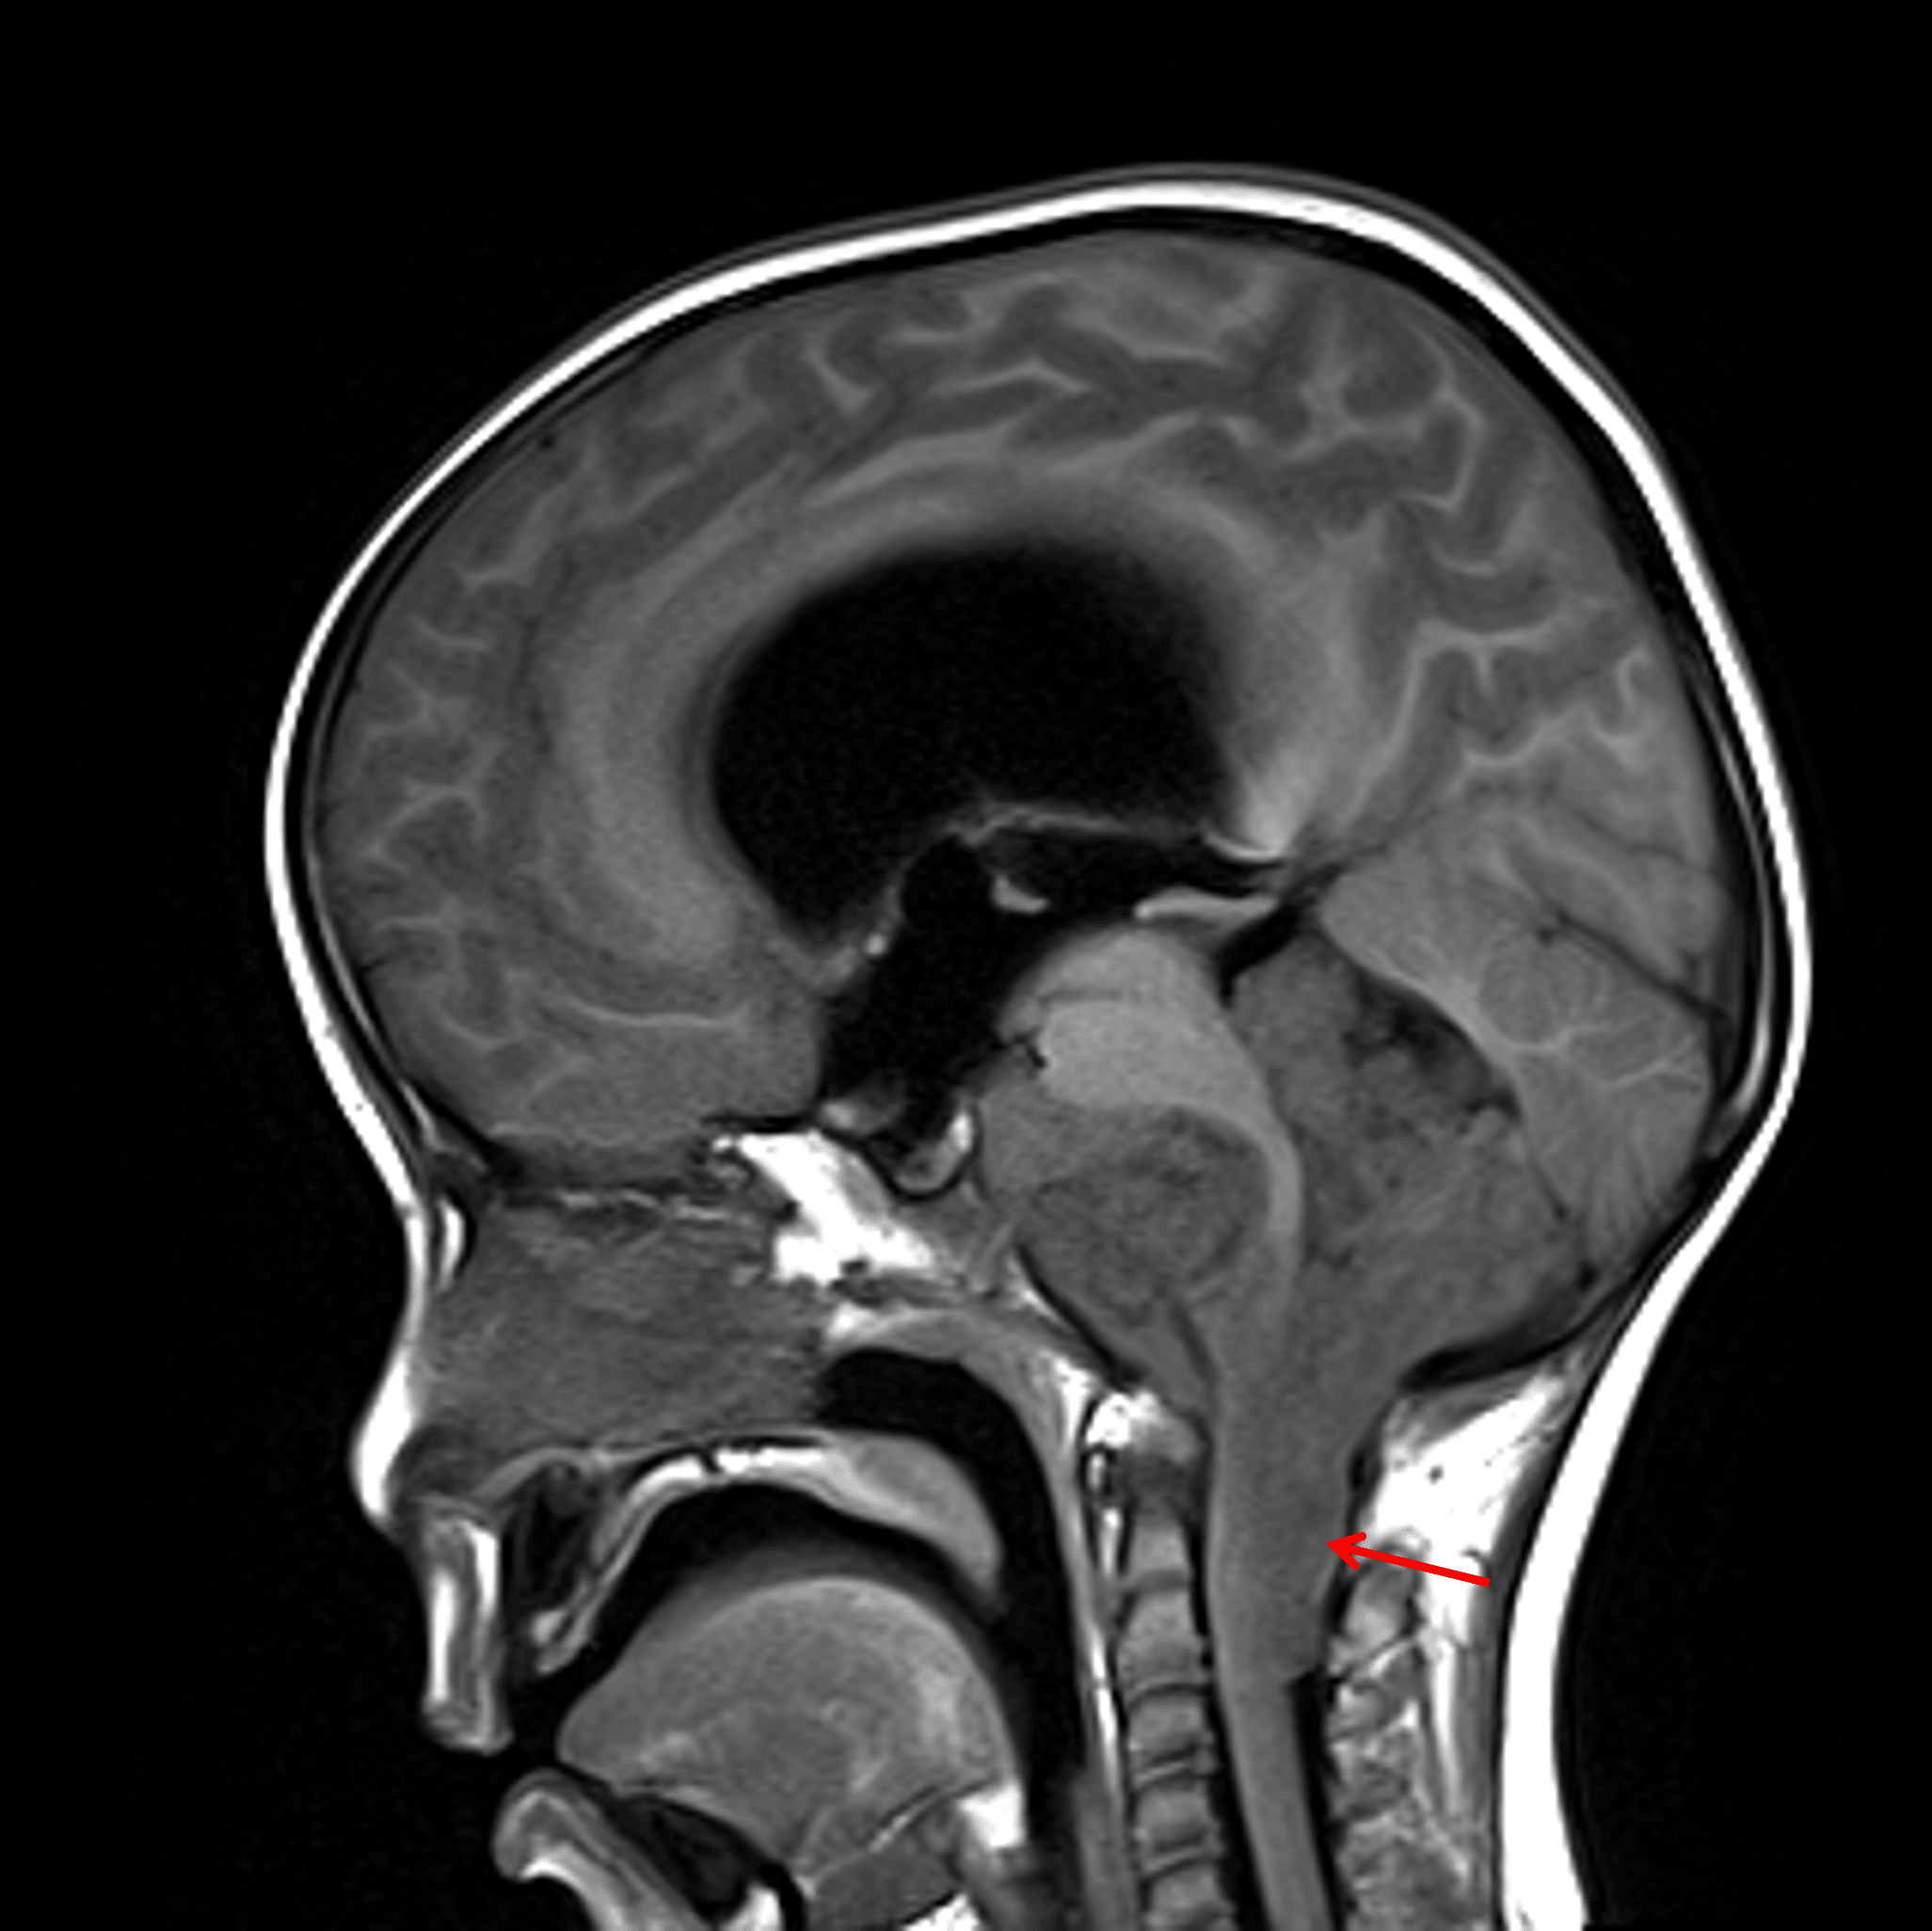

Sagittal T1 precontrast image shows the tumor encasing multiple posterior fossa structures and extending inferiorly within the dorsal aspect of the upper cervical spinal canal (red arrow).